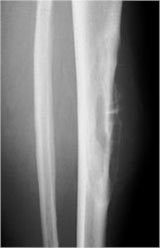

Plain X-Rays:

- Diaphyseal lesion on external surface of bone; medullary canal uninvolved

- Radiolucent mass extending into surrounding soft tissues

- Saucerized cortex with chondroblastic soft tissue mass that is usually primarily radiolucent on plain X-rays

- Periosteal reaction usually most evident feature on surface of bone (Hair on End or Sunburst appearance with spiculated pattern of calcification oriented perpendicular to the bone)